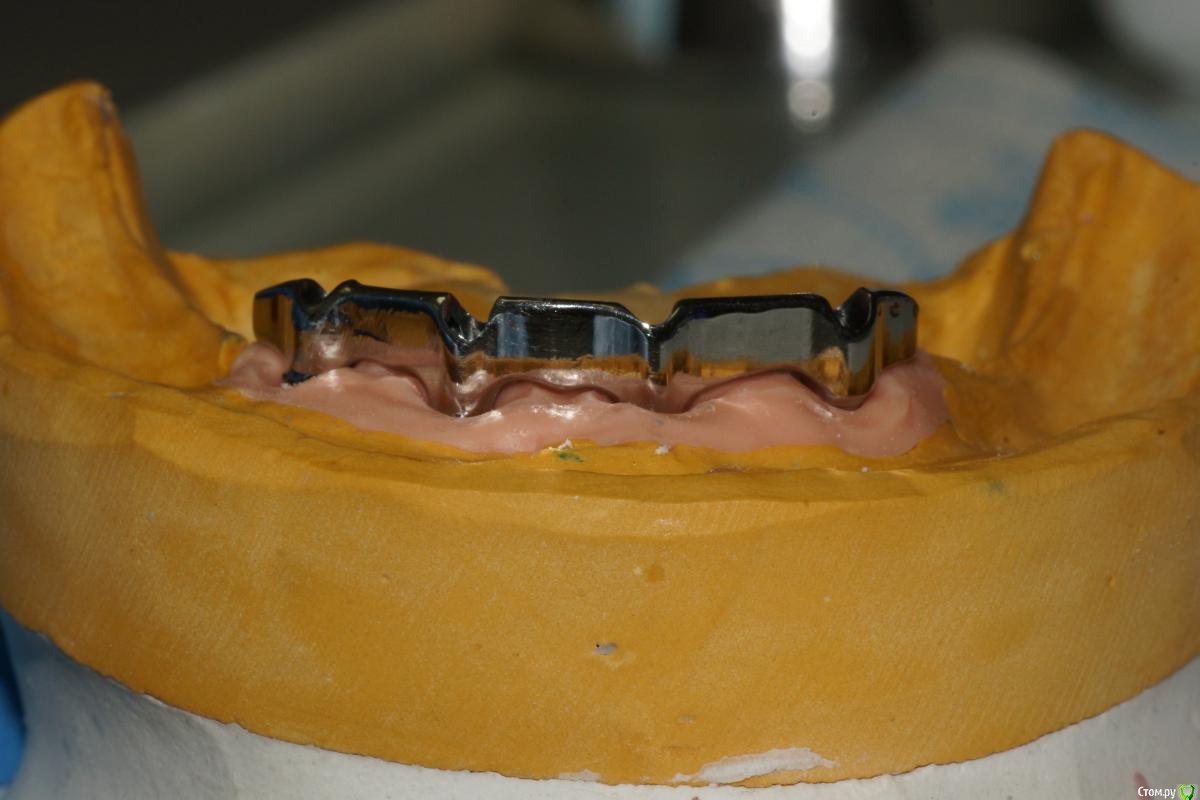

chervoncevdaniil Опубликовано 29 ноября, 2016 Поделиться Опубликовано 29 ноября, 2016 А как вы определяли прикус в данном кейсе?валики на жестком базисе были?на что опирались? Ссылка на комментарий

togrul Опубликовано 29 ноября, 2016 Автор Поделиться Опубликовано 29 ноября, 2016 Добрый день определял на жёстком базисе. На имплантатах опирались на имплантаты. Ссылка на комментарий